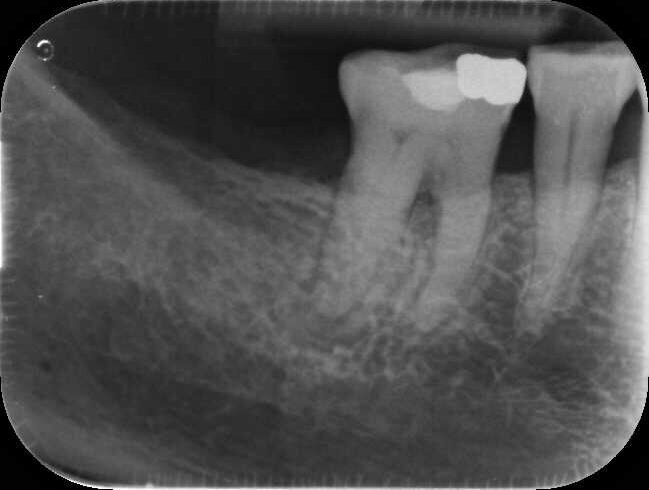

Fig. 14a: Case treated with Bassi Logic controlled memory nickel titanium files. Note the visualization of the third root on this lower molar and conservative canal preparation shape. (Courtesy of Dr. Alex Chan)

Fig. 14b: Case treated with Bassi Logic controlled memory nickel titanium files. Note the visualization of the third root on this lower molar and conservative canal preparation shape. (Courtesy of Dr. Alex Chan)

There are literally dozens of instrumentation systems available globally at this time. One author uses the Twisted File (KavoKerr) (BG) and the other Logic (Bassi Endo) (RM). This notwithstanding, the goals of canal shaping are identical regardless of the system used. Regardless of the instrumentation system used, patency is always sought during canal scouting and instrumentation. Clinicians can debate the relative merits of reciprocation versus rotary motion, optimal Af temperatures (austenite transformation temperatures that control whether a file undergoes the martensitic transformation), controlled memory files ground by CNC machines vs. twisting nickel titanium in R phase along with a multitude of different similar clinical issues. Regardless of these nuances, it is the adherence to basic principles of canal preparation that files create a pathway from coronal to apical to allow irrigant to flow into all of the canal ramifications which clean the root canal system and optimize clinical success.

Goals of canal preparation include keeping the canal centered in its original position within the root structure and keeping the apical foramen at its original position and size. One of the hallmarks of all the cases illustrated is that the apical foramen has been respected. Specifically, it has not been moved, transported, zipped and/or altered in any way. The apical foramen might be thought of as the “North Star” in endodontics. Reaching the apical constriction without transporting the canal and eliminating all debris from the canal and providing a tapering funnel from orifice to apex is a key canal preparation objective.

The final prepared canal shape should be large enough to irrigate and obturate, but not so large as to structurally weaken the tooth. For practical purposes, while treatment philosophies differ, the minimum guidelines for final prepared taper should be .04 and the minimum apical diameter a 30 (depending on the initial size of the foramen). Given the advent of controlled memory nickel titanium there is little indication for larger tapers, especially in fine three-dimensional apical curvatures. As mentioned, patency is essential because its obtainment means that the clinician can always reach the apex during every phase of treatment and its loss means that tissue, toxins and bacteria can remain despite irrigation procedures, especially in the apical third. Apical debris is the harbinger of iatrogenic events including but not limited to canal transportation, zipping, irrigant extrusion and a lack of optimal canal cleaning.